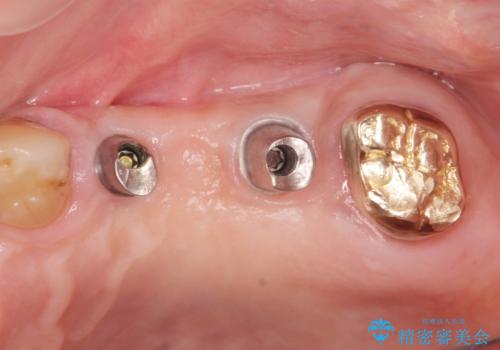

- 奥歯を失い半年間入れ歯を使用してみたが、とにかく咬めない、食事を楽しむことができない!と

咬合機能の回復を求めて来院されました。

しっかりとまた物を噛めるようになるために、インプラントを用いて咬合機能を回復していきます。

- 106.7万円(インプラント×2・チタンカスタムアバットメント×2・ジルコニアクラウン×3・仮歯×3)費用は治療当時の料金となります